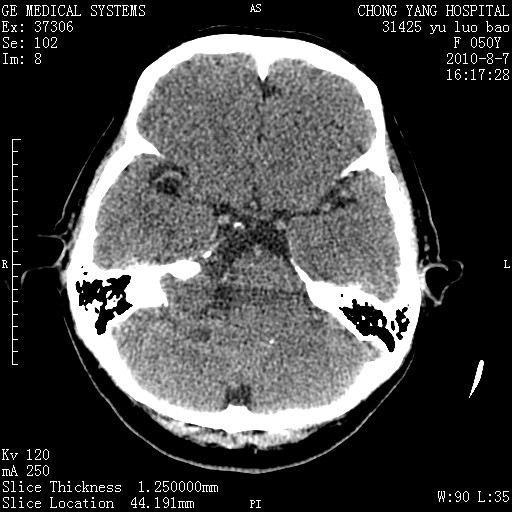

标题: CT28285:听力下降一年,头昏。 [打印本页]

标题: CT28285:听力下降一年,头昏。

右侧内听道扩大、骨质吸收,中脑受压左移,考虑:右侧听神经瘤,建议增强检查。支持!

右侧桥小脑角区等密度占位,内耳道扩大,听神经瘤